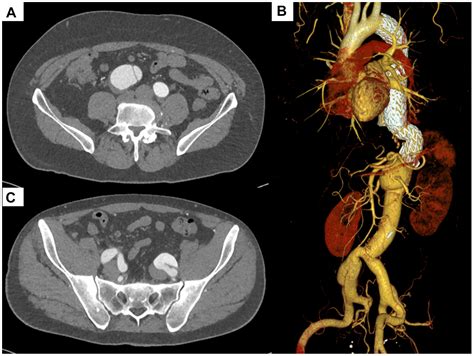

Diagnosing an Iliac Artery Aneurysm typically involves a combination of medical history, physical examination, and imaging tests. The diagnostic process may include:

• Computed Tomography Angiography (CTA): This imaging test provides detailed images of the blood vessels and can help determine the size and location of the aneurysm.

• Endovascular Repair: This minimally invasive procedure involves inserting a stent-graft through a small incision in the groin and guiding it to the site of the aneurysm. The stent-graft reinforces the weakened artery wall and prevents rupture.